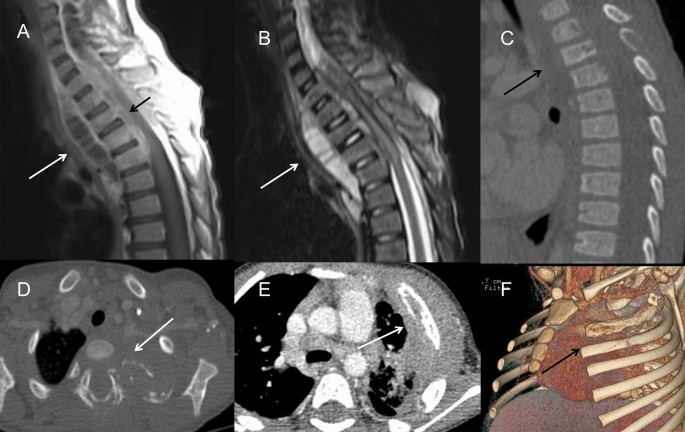

In TB infection (n = 7), the pulmonary infections were more severe and complicated. Masses and nodules of different sizes in the bilateral pulmonary field were identified in 6 patients, while nodular calcification was observed in 3 patients. Some masses and nodules had various levels of heterogeneous enhancement, indicating the existence of caseous necrosis. Large areas of consolidation and ground-grass opacity were common in the bilateral fields, some with multiple small cavities and necrosis within. Two patients presented extensive pulmonary fibrosis and severe emphysema, extensive bronchiectasis, and ipsilateral pulmonary volume loss. Mediastinal and hilar lymphadenopathy enlargement were remarkable in 2 patients, 5 cm in diameter, leading to adjacent bronchostenosis and pulmonary atelectasis. In a 3-year-old boy with TB, paravertebral abscesses extending into the spinal canal and osteomyelitis of the 3rd and 4th thoracic vertebra could be found (Fig. 5A–D). BCG infection was characterized by ipsilateral axillary lymph node enlargement after vaccination and calcifications, which are usually present at 6 months of age, some with surrounding rim enhancement. No obvious pulmonary infection was identified in this cohort.

(A–D) A 3-year-old boy with infection of TB. (A) On CT, the 3rd thoracic vertebra was slightly compressed and the 3rd and 4th thoracic vertebra had multiple small areas of osteolysis (long arrow). (B) On T2WI image, paravertebral abscess extending into the spinal canal and compressing the thoracic spinal cord could be found (long arrow). (C) The abscess wall was markedly enhanced on post-contrast T1WI sequence (long arrow). (D) On axial CT image, the osteolysis and expansion of the left first rib and vertebral plate were found (long arrow). (E,F) A 2-year-old boy with fungi infection. On CT images, osteomyelitis of the left 2nd rib and surrounding soft tissue swelling were showed (long arrow). The adjacent lung infection and pleural thickening were also noticed.

The lungs have been found to be the most affected organs, with various and complex manifestations in CGD patients1,10,11. Radiologic findings can reveal multiple manifestations for the evaluation of disease progress. The findings of this paper were consistent with previous studies, including infiltration, consolidation and pulmonary nodules in acute infection12. Nodules were most common in CGD, ranging from 1 to 5 mm with or without a halo sign, which were usually associated with fungal infection and are distinct from lymphoma or metastatic tumors. The lower lobes of both lungs are the most frequent location of consolidation and ground-grass opacity. Abscesses and cavity formation have been reported to be found in up to 20% of patients13. Cavities usually present with a smooth wall with no mural nodule. Lung infections in CGD patients typically have a protracted course with a tendency to recurrence, which may be complicated with pulmonary fibrosis and bronchiectasia14,15. Fibrotic changes and bronchiectasis are usually seen in patients above 8 years old, mostly in the lower lobes, probably caused by chronic infection and inflammatory response5. In our cohort, almost 2/3 of patients only had a mild degree of pulmonary scarring and local bronchiectasis, possibly because the children involved in the study were at a younger age and were under effective clinical treatment. Persistent hilar or mediastinal lymphadenopathy was detected in most of our patients, especially left axillary lymphadenopathy, which is highly suggestive of BCG infection. Chest wall invasion, including osteomyelitis of the ribs and vertebral bodies, has also been reported as a specific manifestation associated with adjacent pulmonary infection4,13,16. Aspergillus is the predominant source of chest wall osteomyelitis (Fig. 5E,F), followed by TB17. Six of our patients had chest wall invasion, with lung masses and consolidation in the adjacent lung lobes. Chest CT may reveal osseous erosion with periosteal reaction and soft tissue masses. MRI can display bone marrow signal abnormalities and surrounding soft-tissue inflammation, which can serve as a useful tool to make an accurate assessment of the severity of the disease18.